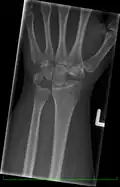

Left hand x-ray with Kienbock's Disease showing 4 mm negative ulnar variance and Kienbock's Disease Stage IIIB -

X-ray showing stage IIIB on right wrist, with ulnar impingement. -